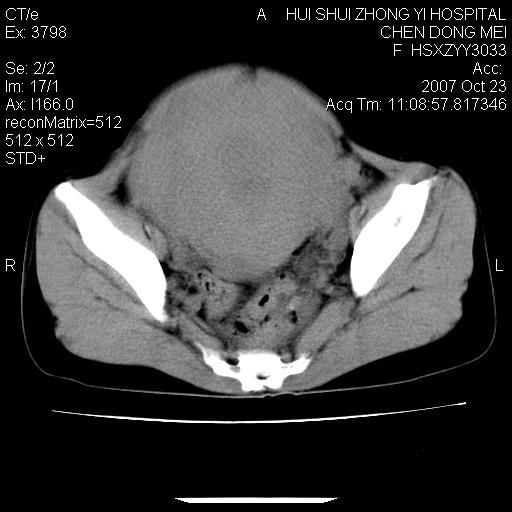

标题: CT10156:女.43岁,发现中下腹部包都块2年 [打印本页]

标题: CT10156:女.43岁,发现中下腹部包都块2年

发现中下腹部包都块2年。2年来月经不规律。

腹腔巨大软组织密度影,边缘光滑,包膜完整,内囊变坏死。腹膜后及盆腔内淋巴结肿大。结合病史考虑卵巢癌可能性大。

病变巨大,呈囊实性改变,包膜较厚且完整,内见分膈,周围脏器明显受压移位,病变与左侧附件关系密切,考虑来源左侧附件的囊腺瘤,不除外癌变可能;畸胎瘤可能性较小。

病变巨大,呈囊实性改变,包膜较厚且完整,内见分膈,周围脏器明显受压移位,病变与左侧附件关系密切,考虑来源左侧附件的囊腺瘤,盆腔内见肿大淋巴结,不除外癌变可能。

病变巨大,呈囊实性改变,包膜较厚且完整,内见分膈,周围脏器明显受压移位,病变与左侧附件关系密切,考虑来源左侧附件的囊腺瘤,不除外癌变可能